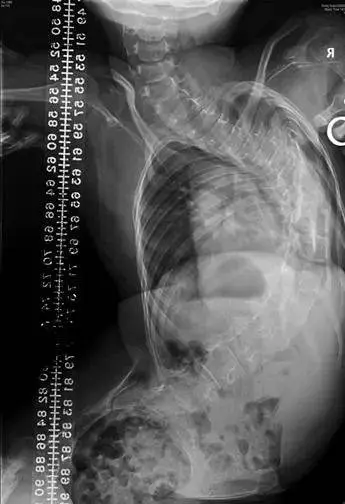

神经肌肉型脊柱侧弯(图 4 , 5) 成因包括继发性的神经或肌肉疾病,如脑瘫、脊髓创伤、肌肉萎缩症、脊髓性肌肉萎缩症和脊柱裂。这类的脊柱侧弯通常迅速演化,往往需要手术治疗。

图 4 患有脊髓性肌肉萎缩症的女孩出现严重及大范围的胸椎侧弯。留意明显侧倾的盆骨及其不良坐姿。

图 5 同一患者坐著拍摄的正前方 X 光造影。留意 X 光造影如何显示骨盆侧倾的真正严重程度。这情况最好接受手术治疗,令患者能坐得舒适。